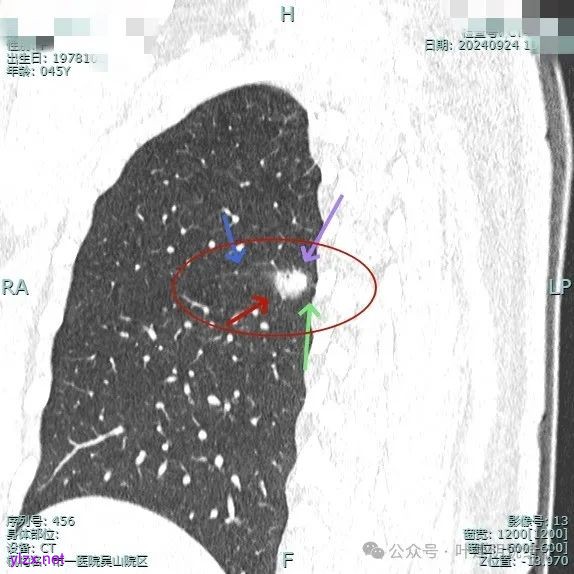

时间很快到了2025年3月,结友又来我门诊复查,我还以为她在别处开了刀了呢,结果并没有,说是与家人商量后决定吃中药三个月看看能不能好。我们来看看再复查的情况,中药有没有起作用:

总体感觉三处病灶边缘的淡磨玻璃成分好转不太明显了,实性成分较前略显致密点,大小与形态是说不上显著变化的。所以有几点可以肯定:1、消炎没有效;2、中药没有用;3、考虑多原发肺癌,且为浸润性腺癌可能性大些,得手术!